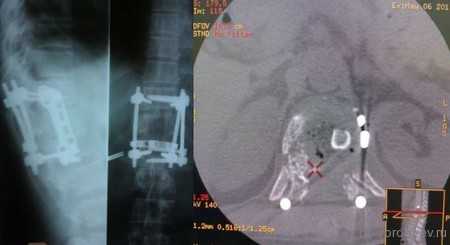

Представлены КТ пациента до и после оперативного лечения по поводу осложненного перелома пятого шейного позвонка. Выполнена корпорэктомия пятого шейного позвонка с комбинированным корпородезом аутокостью из подвздошного гребня и пластиной китайского производства.

На данных томограммах представлен нестабильный перелом тела Тн12 позвонка

Первым этапом выполнена ламинэктомия с транспедикулярной фиксацией китайской системой, а затем проведена корпорэктомия, корпородез аутокостью и тораколюмбальной пластиной китайского производства.